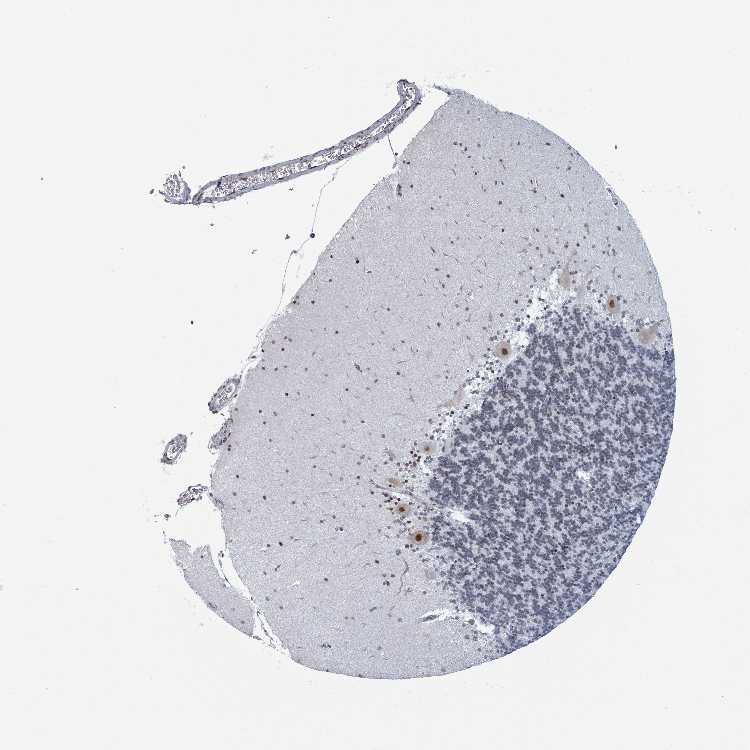

CEREBELLUM - Antibody stainingi

Antibody staining in the annotated cell types in the current human tissue is reported as not detected, low, medium, or high, based on conventional immunohistochemistry profiling in selected tissues. This score is based on the combination of the staining intensity and fraction of stained cells.

Each image is clickable and will lead to virtual microscopy that enables deeper exploration of all samples and also displays staining intensity scores, fraction scores and subcellular localization as well as patient and tissue information for each sample.

Antibody HPA051455

Purkinje cells High

Cells in granular layer Medium

Cells in molecular layer Medium